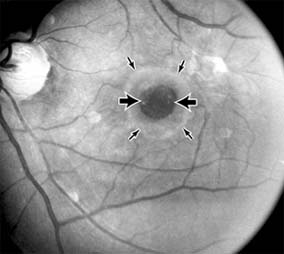

Presumed Ocular Histoplasmosis Syndrome (Figures 10-5, 10-6 and 10-7)

In this disease, serous and hemorrhagic detachments of the macula are associated with multiple peripheral atrophic chorioretinal scars and peripapillary chorioretinal scarring (see Chapter 7). The syndrome usually occurs in healthy patients between the third and sixth decades of life, and the scars are probably caused by an antecedent subclinical systemic infection with Histoplasma capsulatum. The macular detachments are due to subretinal neovascularization, and the visual prognosis depends on the proximity of the neovascular membrane to the center of the fovea. If the membrane extends inside the foveal avascular zone, only 15% of eyes will retain 20/40 vision. A macular scar may change over time, and 10% of patients with normal maculae will develop new atrophic scars in this region. The relative risk of developing macular subretinal neovascularization in the second eye of an affected patient is significant, and these patients should be instructed in the frequent use of the Amsler grid and the importance of prompt examination when changes are detected.

Figure 10-5

Figure 10-5: Presumed ocular histoplasmosis syndrome with active disease (large arrows) and an inactive pigmented macular scar (small arrow). Peripapillary pigmentation (curved arrow) is also present.

Figure 10-6

Figure 10-6: The early fluorescein angiogram shows an inactive hypofluorescent scar (small arrow) and the characteristic lacy hyperfluorescence of subretinal neovascularization (open arrows).

Figure 10-7

Figure 10-7: Late fluorescein leakage from macular subretinal neovascularization in a patient with presumed ocular histoplasmosis syndrome.